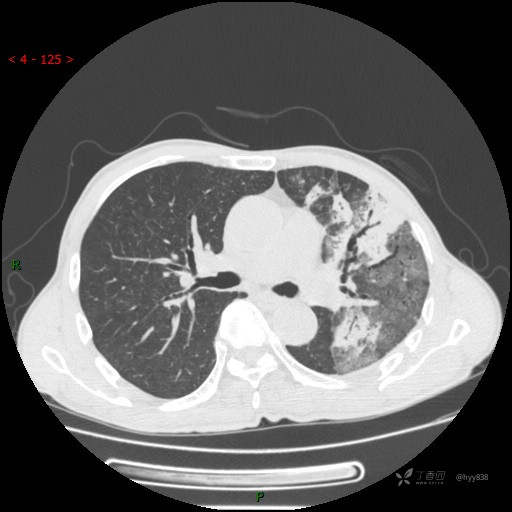

四天后复查(怀疑肺栓)